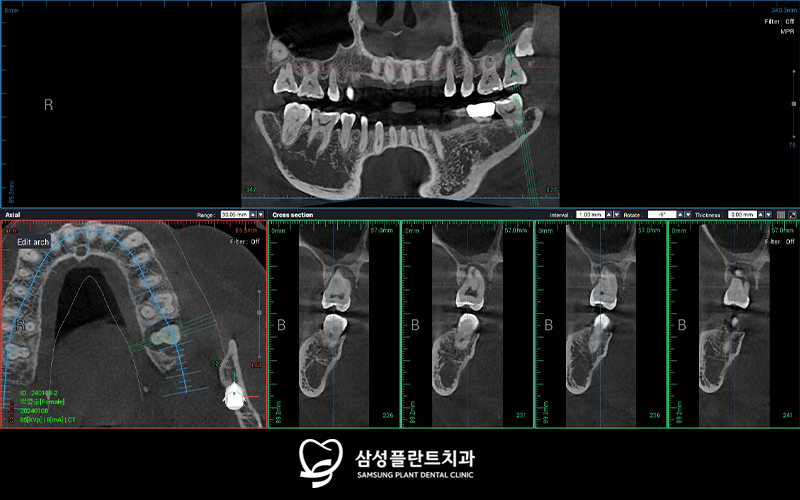

3D-CT 정밀 분석을 통해

식립할 임플란트의 위치 및 방향등을

꼼꼼하게 체크한 후

수술을 진행했습니다.

발치 및 뼈이식을 진행하고

4개월의 충분한 회복 기간을 거친 뒤

임플란트 수술을 진행한 모습입니다.